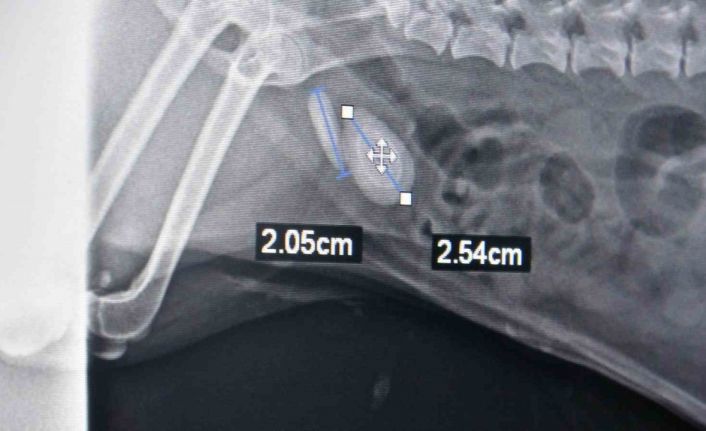

Tokat’ta bir evcil hayvan sahibi köpeğinin idrar yapamaması, idrardaki renk değişiklikleri, idrarda kan olması, idrara gitme isteği ama idrarını yapamaması şikayetleriyle veteriner hekime başvurdu. Yapılan muayenelerin ardından köpeğin idrar kesesinde taş olduğu tespit edildi. Yapılan operasyonla köpeğin idrar kesesindeki üç taş çıkarıldı. Ameliyatı gerçekleştiren veteriner hekim Muhammet Ahmet Gülden, "Evcil hayvan idrar yapamama şikayetiyle kliniğimize başvurdu. Yaptığımız ultrason muayenesinde taş tespit ettik. Ondan sonra yaptığımız röntgen muayenesi ile taşı tam olarak teşhis edip, ameliyat kararı aldık. Toplam teşhis ettiğimiz taş iki taneydi ama ameliyat yaptığımızda üç tane taş çıkardık. 2 buçuk, 2 ve 1 santimetrelik bu taşları sistotomi ameliyatıyla aldık. Ameliyat olan evcil hayvan terrier ırkı, 7 veya 8 yaşında bir köpek. Sürekli tuvalete gidip idrarını yapamama şikayetiyle geldi. İdrar kesesinin yankısı, idrarda taş kristaller, kum, enfeksiyon hastalıkları, bunlar da benzer şikayetlerle olabiliyor. Tabii hasta sahibinin bunu anlayabileceği en önemli belirti idrardaki renk değişiklikleri, idrarda kan olması, idrara gitme isteği ama idrarını yapamaması. Evcil hayvan sahiplerinin bu durumla karşılaştıkları zaman ilk yapması gereken şey fazla zaman kaybetmeden bir veteriner hekime başvurmaları olmalıdır. Hayvanın uzun süre idrarını yapamaması böbrek yetmezliğine sebebiyet veriyor. Böbrek yetmezliği ölüm durumuna kadar götüreceği için hayati risk oluşturuyor. Bazı hayvanlarda yatkınlık var. Bazı ırklarda taş oluşması ile alakalı yatkınlıklar var. Onun dışında beslenme bozuklukları gibi olgular da etkili olabilir. Erkek hayvanlar dişi hayvanlara göre taş ve idrar kesesi yangısına daha yatkındır. Kediler ve köpekler, özellikle kısırlaştırılmış olan hayvanlar mutlaka kısır kedi mamaları yemeleri gerekiyor. Bunlar dışında hazır su tüketmeleri de önemli bir durumdur. Çeşme suyundan ziyade hazır su daha sağlıklı olacağından, bunlara dikkat etmeleri daha iyi olur. Şu an ameliyat olan köpek iyi durumda, idrarını yapabiliyor" dedi.